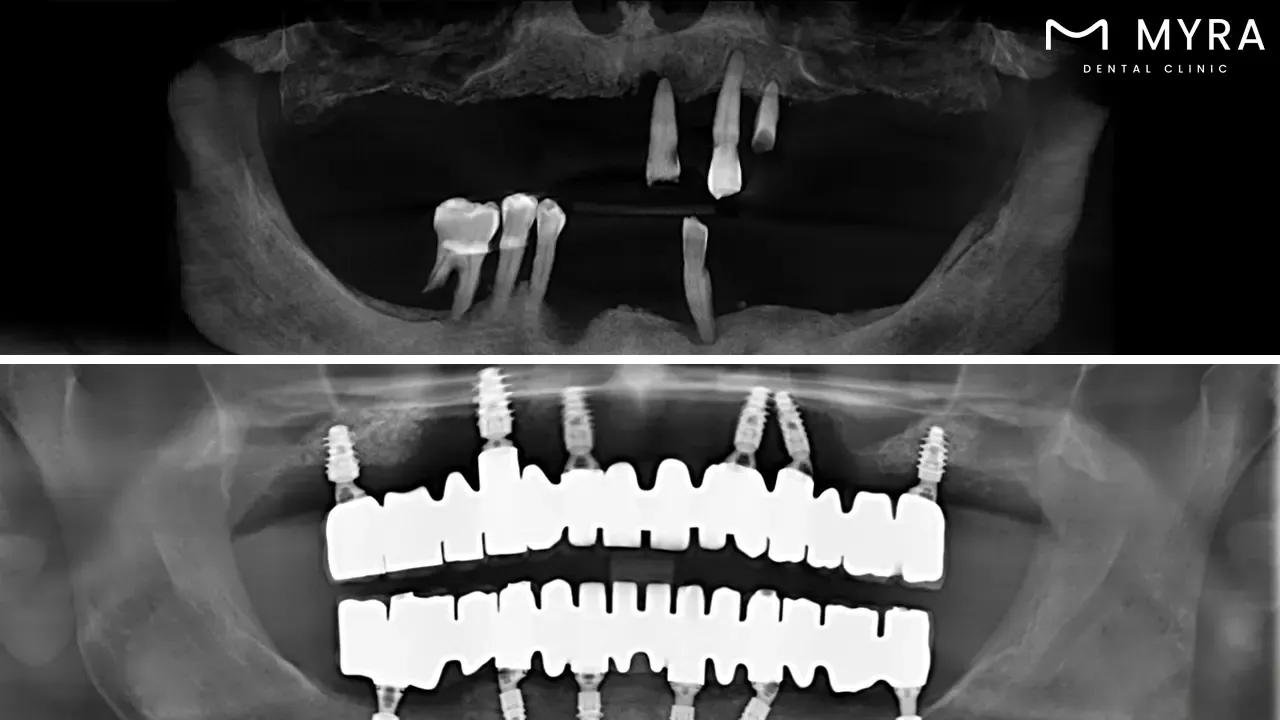

Full mouth rehabilitation, often known as full mouth reconstruction or smile restoration, is a comprehensive therapy technique. Full mouth rehabilitation fully tackles many dental disorders, aiming to restore function and aesthetics to the entire mouth.

Full Mouth Rehabilitation in Turkey: Full mouth rehabilitation, known as full mouth reconstruction or smile restoration, is a complete therapeutic method that aims to restore function and aesthetics to the entire mouth.

Full mouth rehabilitation is a comprehensive and highly individualized dental treatment plan in Turkey. Full mouth rehabilitation is known as full mouth reconstruction or full mouth restoration. Its major goal is to completely restore an individual's oral cavity's function, attractiveness, and overall health. The all-encompassing approach includes a variety of restorative, aesthetic, and even surgical dental operations that are thoroughly performed to address a wide range of dental disorders and concerns.

A full mouth rehabilitation with four dental implants and a full bridge of 12 teeth usually costs around £18,060 in UK. The total price includes the dental implant costs of £7,800 and the full bridge restoration costs of £10,260. However, the same treatment, known as All-on-4 in Turkey, is approximately 60% more affordable in Turkey, offering significant savings without compromising quality. Individuals must contact their dentist to analyze their specific dental requirements and goals to receive an accurate and individualized cost breakdown.

Full mouth rehabilitation with dental implants and a full bridge provides several important benefits. Full mouth rehabilitation offers a holistic solution for people who have dental disorders, addressing functional and aesthetic concerns in a single treatment plan. The use of dental implants provides a sturdy and stable basis for the complete bridge, improving chewing and speaking skills. The entire bridge of 12 teeth provides a natural-looking smile makeover, which results in increased self-confidence and a better overall quality of life. Patients enjoy the benefits of dental implants and well-crafted bridges for many years with proper care, making it a beneficial long-term investment in their oral health and well-being.

There are downsides to consider while whole mouth rehabilitation with dental implants and a full bridge has many advantages. Financial commitment is a barrier for other people in UK and USA. The treatment time is rather long, spanning several months to get the desired results. The surgical part of dental implant insertion requires planning, and there are patients who have temporary discomfort or healing time. The permanent nature of some operations, such as tooth extraction for implants, needs careful preparation and consultation with the dentist before proceeding.

The extensive process takes several weeks to up to six months or more. Full mouth rehabilitation requires numerous appointments, each dedicated to a specific treatment, rigorous planning, and the healing and integration period required for dental implants. The lengthy timeline is due to the requirement for optimal healing, the procedure's step-by-step structure, and the tailored character of whole-mouth rehabilitation. Patients must talk with their dentist in Turkey to determine a realistic timescale adapted to their unique case and treatment plan while keeping in mind that getting the desired outcomes takes several months.